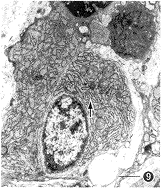

第2次冷冻后上皮呈柱状或高柱状,细胞器丰富,游离端有密集微绒毛或纤毛,纤毛短而整齐,微管和中心管清晰(图8)。固有层浆细胞、淋巴细胞和巨噬细胞数量增多,浆细胞内粗面内质网扩张,网池内充满中等电子密度的絮状物(图9),说明蛋白合成旺盛。小血管内线粒体数量增多。

图9 第二次冷冻后鼻粘膜透射电镜图像,可见浆细胞内粗面内质网扩张,网池内充满絮状物(

)标尺=1μm